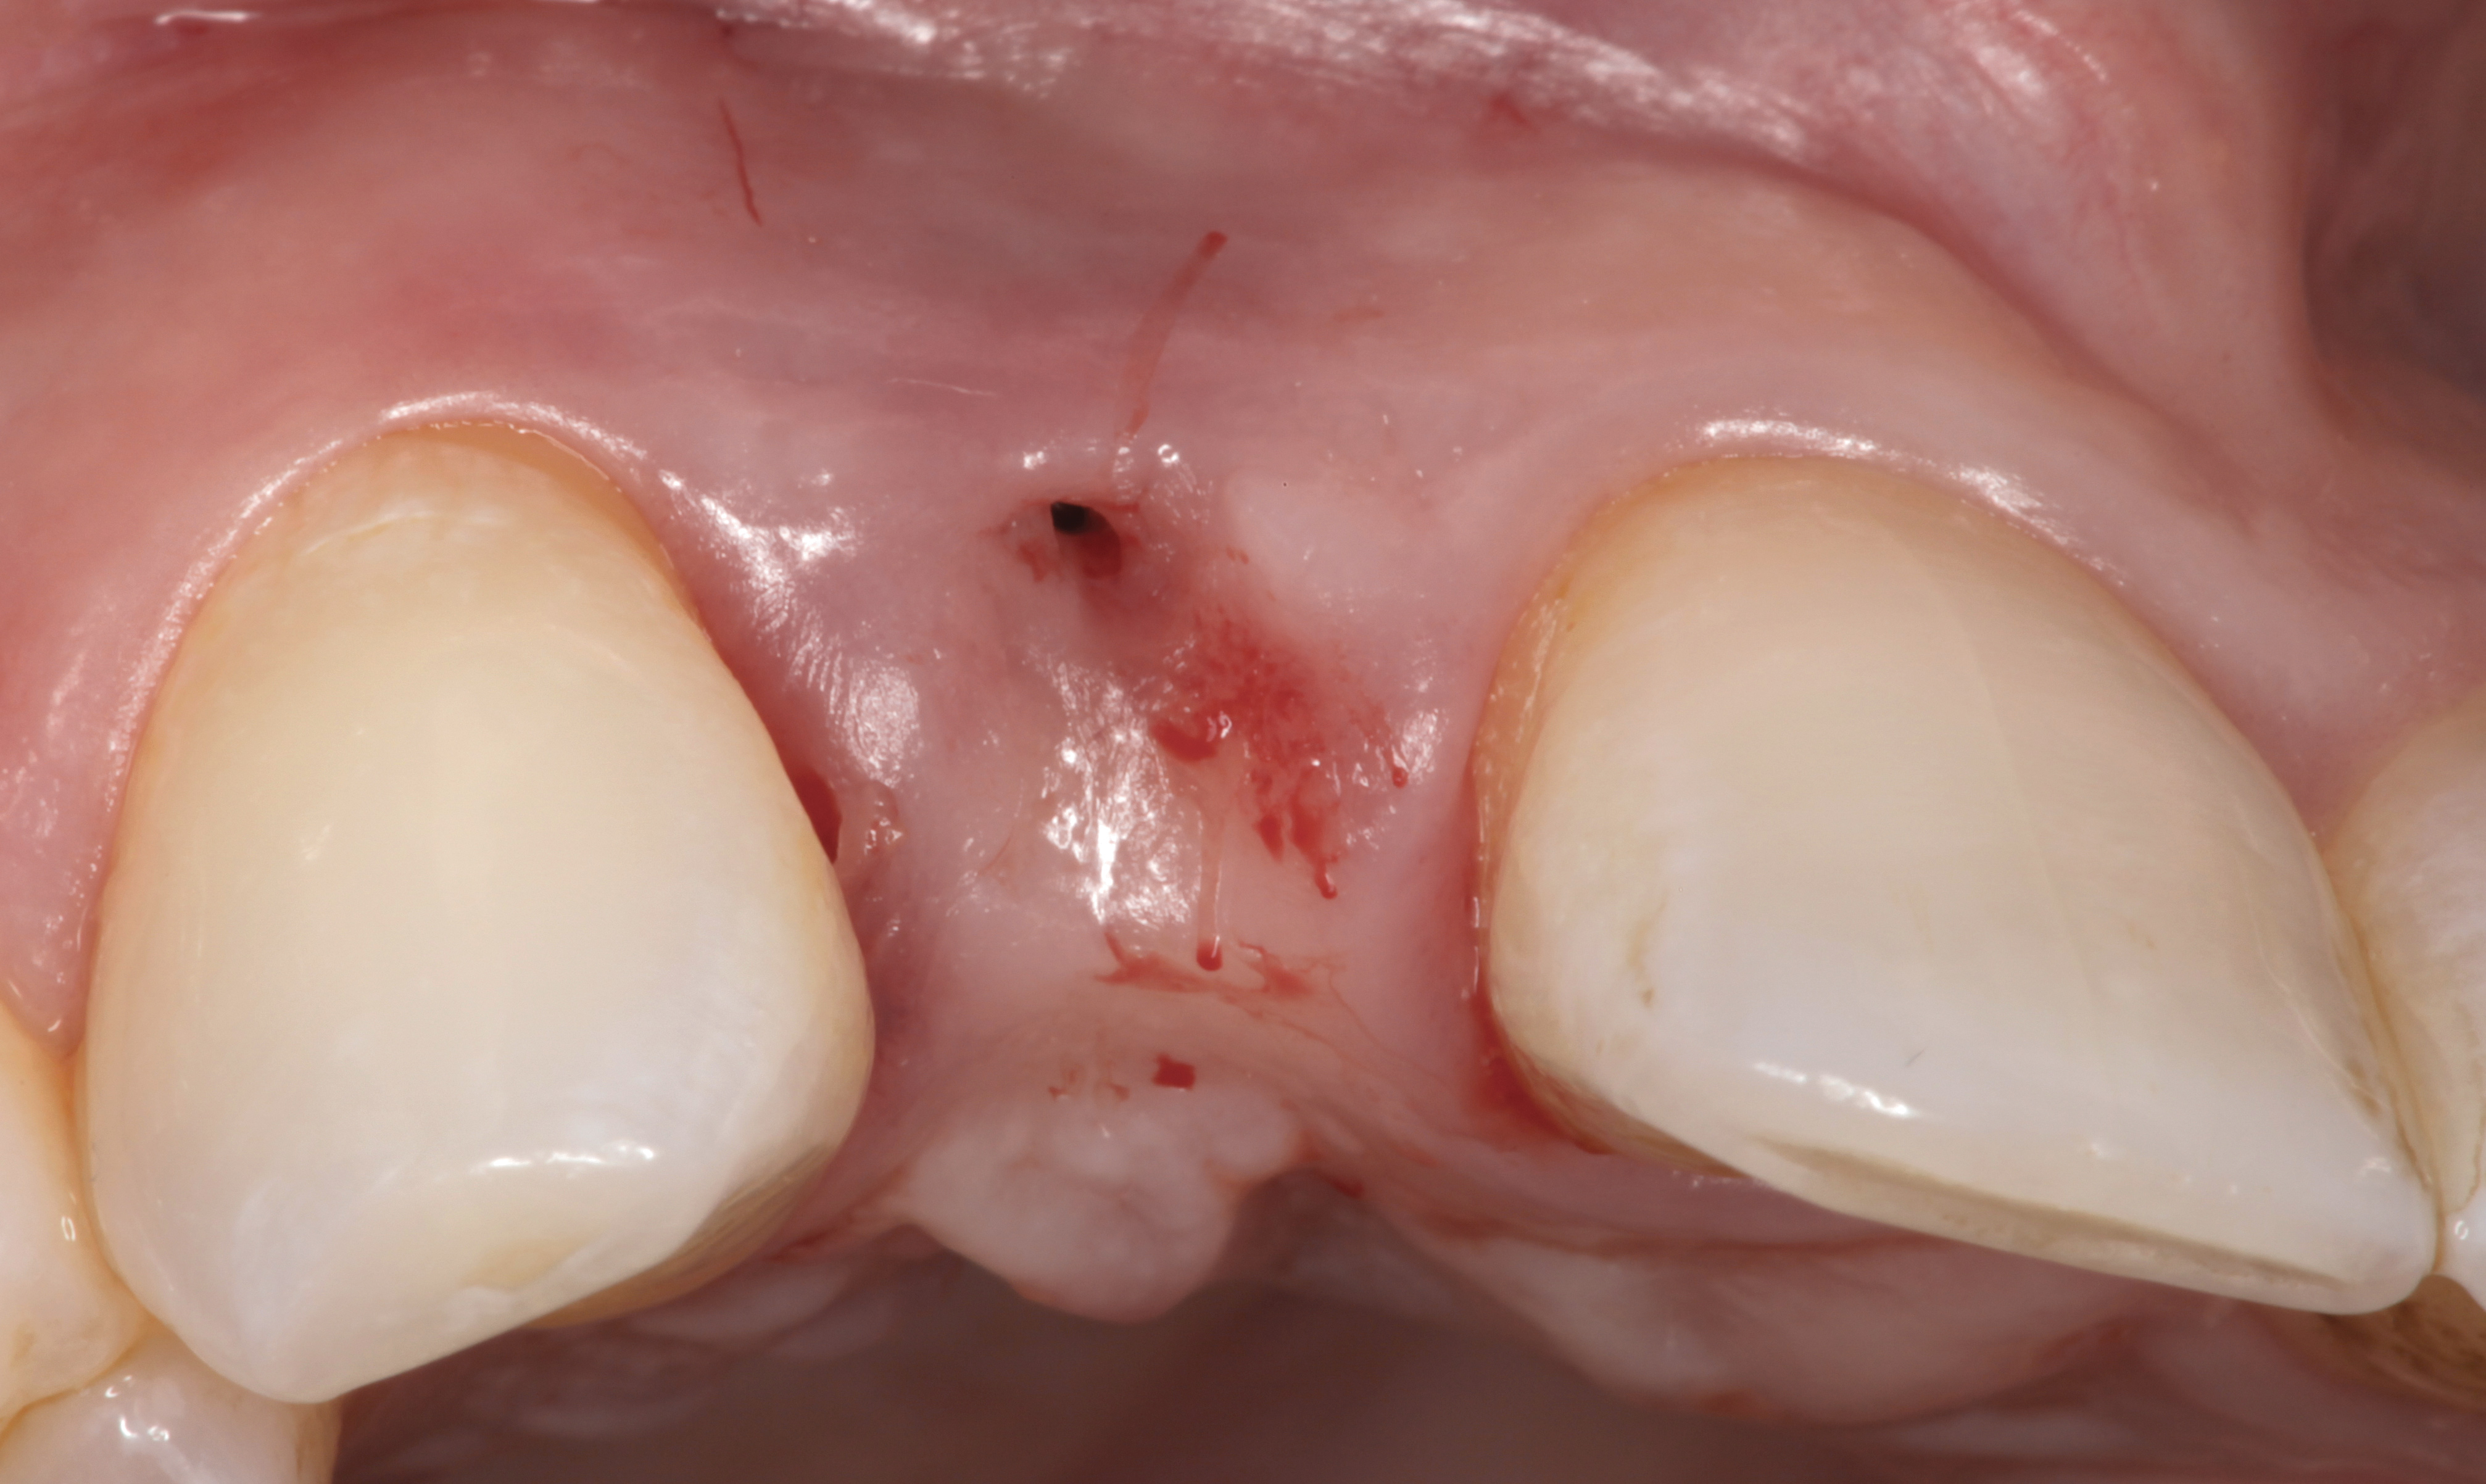

The crown and screw-retained custom abutment were removed, and a surgical cover screw was placed into the implant, thereby allowing spontaneous gingival augmentation in situ (Figure 33 and Figure 34). Note that the lingual aspect of the implant site was significantly more coronal than the labial aspect, which was positive because the defect would be limited to a facial–lingual defect. A fixed RBR bridge was cemented on the adjacent teeth and used as a tooth-supported transitional provisional restoration (Figure 35). A few weeks were allotted to let the soft tissue heal and migrate around the cover screw (Figure 36) to see if there would be complete coverage, thereby allowing a soft-tissue augmentation procedure to be performed with primary flap closure as in clinical scenario No. 2. The major obstacle in achieving a positive tissue response was that the implant depth was also deficient because the implant–abutment connection was at the level of the free gingival margin. It was decided that the best treatment option would be to remove the implant. A high-powered reverse-torque device (Fixture Remover Kit, NeoBiotech, www.neobiotechus.com) was used to remove the implant atraumatically (Figure 38 through Figure 41). The implant socket was allowed to heal for several months not unlike an extracted tooth (Figure 42). A new implant was placed in a better position from both a restorative and esthetic perspective (Figure 43), and after a few months of healing, a new crown was made (Figure 44). A satisfactory functional and esthetic result was achieved (Figure 45 and Figure 46) without employing pink porcelain.

Fig 36. Two weeks after RBR placement, the soft tissue did not adequately cover the implant. The problem was in poor implant angulation and proper depth to allow the soft tissues to cover over.

Figure 36